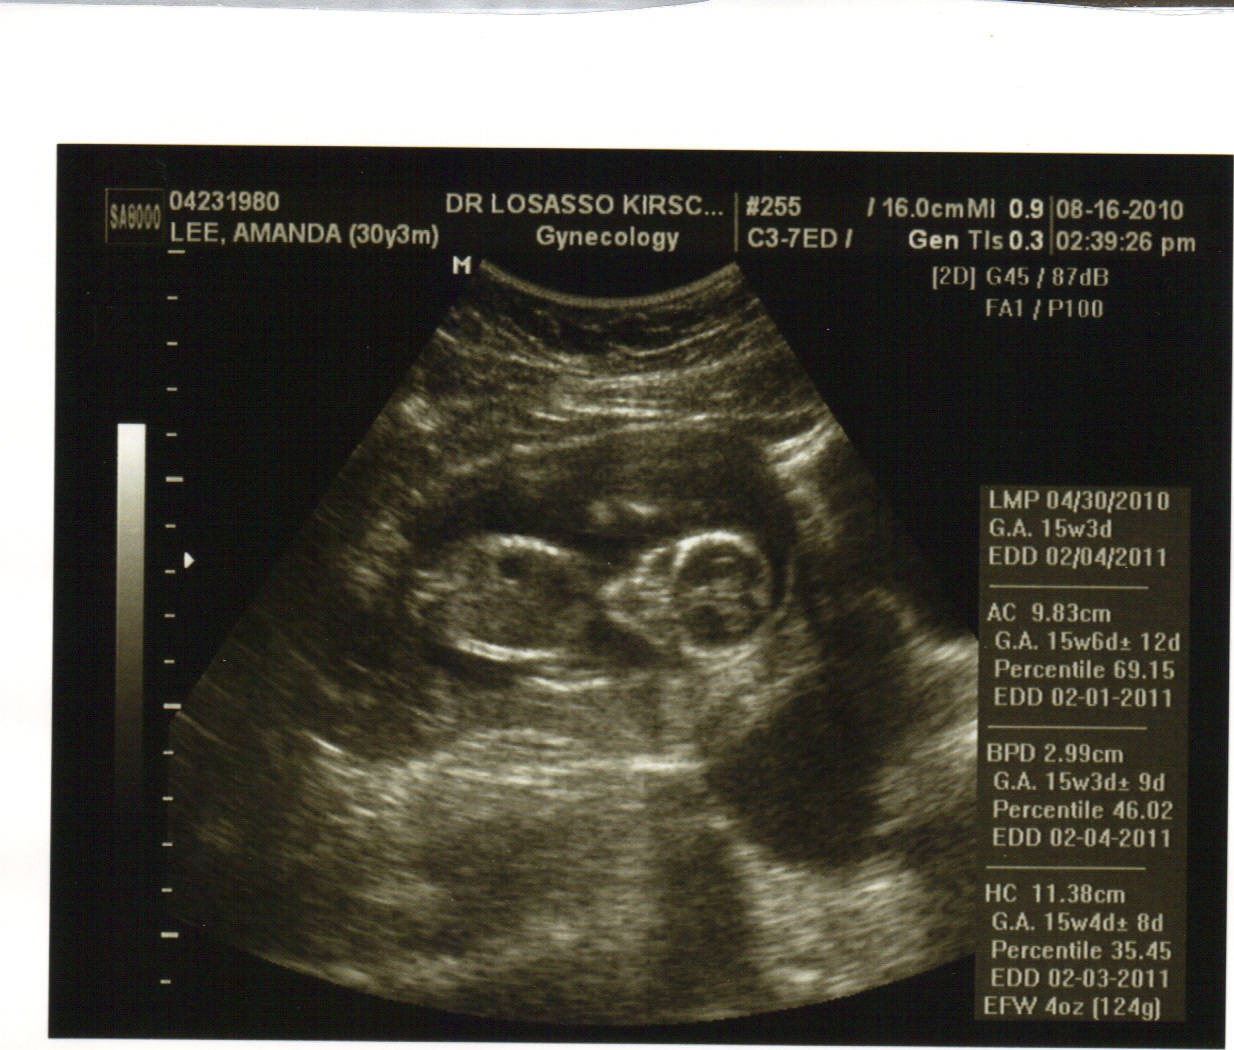

*Successful Surgery:God used Dr. Tate to successfully remove the cyst from my body (and unfortunately my left ovary too). It ended up being the largest cyst she has seen in a pregnant woman and was very glad to get it out.

*Hearing Baby Lee's heartbeat:it was the first thing I asked about when I woke up in recovery. I will never forget that moment even though I probably wasn't all there. Irena was by my side, already checking to see if I was having any contractions and found our precious baby's heartbeat. I was so relieved and happy that I started crying and hyperventilating. The nurses had to calm me down. It was one of the most beautiful moments for me. Later in the day, my Mom and Grandma got to hear it for the first time. That was another beautiful moment for me, seeing my Mom's ear to ear smile!